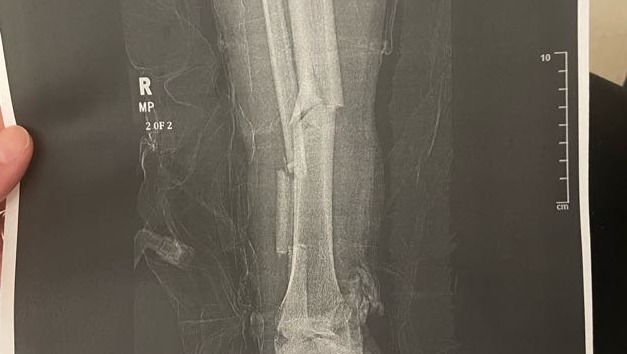

He slipped and fell 40 feet into a big rock lodged on the cliffside, and his gear stopped him from taking the rest of the fall down the mountain. He shattered his fibula and broke his tibia. His partner immediately called for EMS. Kris started to go into shock while still on the wall and rope, but his partner was able to lower them both down to the closest cliff to help administer first aid to stabilize him.

When they reached the bottom, there were many other climbers who so graciously came to his aid and stayed with him while they waited for EMS. He is OKAY, and luckily there were no other significant injuries, and he was able to get the care he needed. He had emergency surgery that was successful in resetting his leg, and he’s back at home recovering. They ended up putting a titanium rod down the middle of his tibia and a plate for the shattered fibula.